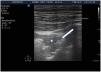

Al iniciar la interpretación de la imagen lo primero que tendremos que identificar es la línea pleural, que aparece como una estructura hiperecoica localizada entre las dos sombras acústicas que generan dos costillas consecutivas. Colocando el transductor perpendicular a las costillas obtenemos el denominado «signo del murciélago» o bat sign (fig. 2) y el deslizamiento entre la pleura visceral y parietal dará lugar a lo que se denomina sliding o «deslizamiento pleural» (vídeo 1)5,6.